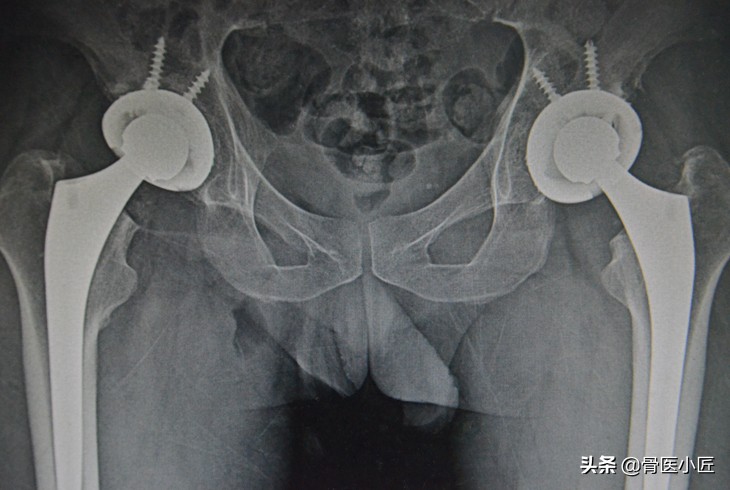

回顾当年的SARS,至今已经过去17年,在那场没有硝烟战争中虽然人类最终取得了胜利,但很多SARS患者因为治疗过程中因为大量使用激素,后期导致很多严重的并发症的发生,他们的生命虽然最终得以保留,生活质量却严重下降;激素导致的股骨头坏死,使他们不得不进行髋关节置换手术,耗尽财力,后半生仍要承受无尽的痛苦。

很多SARS肺炎存活的患者因股骨头坏死不得不选择双侧全髋关节置换术